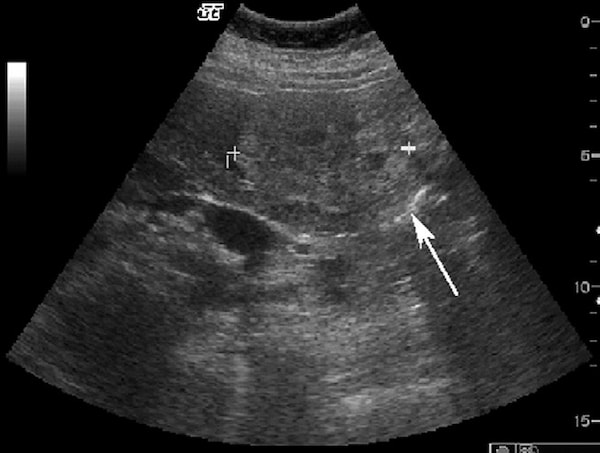

Hemangioma là u gan lành tính thường gặp nhất. Hemangioma thường gặp ở phụ nữ trẻ và 15-20% nhiều ổ. Mô học cho thấy một loạt các hồ máu và kênh mạch, các tổn thương lớn hơn tạo ra các vùng huyết khối và xơ. Siêu âm thấy một khối tăng âm, đồng nhất, giới hạn rõ, tăng âm phía sau yếu (Hình 1). Các tổn thương lớn hơn (>6cm) có thể không đồng nhất và giảm âm do huyết khối, hoại tử và thoái hóa nang. Các dấu hiệu CT cản quang gồm tăng quang dạng nốt ngoại vi ở thì động mạch với lấp đầy hướng tâm dần trong tổn thương ở thì tĩnh mạch cửa và thì muộn (hình 2). Vôi tĩnh mạch (phlebolith) có thể thấy trong tổn thương ở 15-20% trường hợp (Hình 2). MRI cho thấy tăng tín hiệu trung bình trên T2W, thường ít hơn so với nang đơn thuần, tín hiệu thấp trên T1W. MRI sau tiêm thuốc cho thấy bắt thuốc dạng nốt gián đoạn phía ngoại vi ở thì động mạch, đó là đặc điểm điển hình của hemangioma (Hình 3). MRI thì tĩnh mạch và thì muộn có thể thấy các nốt bắt thuốc lớn dần và hợp lưu với lấp dầy trung tâm ở các mức độ khác nhau tương tự như CT.

Hình 1. Nữ 45 tuổi, hemangioma ở thùy gan trái Siêu âm cắt ngang thấy khối 6cm, tăng âm không đồng nhất, giới hạn rõ (mũi tên).